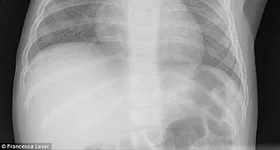

Părinții Isabellei Rees, fetița care a murit după ce a înghițit o baterie, lansează acuzații grave și spun că medicii de la Melbourne’s Sunshine Hospital au refuzat să-i facă Bellei o radiografie. Asta în pofida faptului că fetița se simțea foarte rău, prezentând vârsături cu cheaguri de sânge.

Isabella Rees a murit pe data de 4 februarie 2015, la spitalul Sunshine din Melbourne, Australia, după ce a înghițit o baterie tip ”nasture” AG 13. Mama sa s-a prezentat cu ea la medic, încercând, de trei ori, să îi facă acesteia o radiografie, numai că medicii au tratat simptomele cu superficialitate, consemnează dailymail.co.uk.

În timpul anchetei declanșate după moartea fetiței, tatăl acesteia a declarat că a fost sigur că medicii nu vor crede varianta părinților. Totuși, o radiografie ar fi lămurit această problemă medicală care s-a transformat într-o tragedie.

Suplimentar, mama fetiței este de părere că politica spitalului – prin care părinții ar fi trebuit să prezinte dovezi care să confirme că micuța a înghițit bateria – este una absolut greșită.